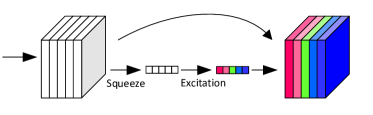

3.2. Squeeze-and-Excitation Block in DenseNet

In classical CNNs, it is difficult to model the interdependency between channels using convolutional filters, which are initialized and trained independently. However, the cross-channel dependency is widely existing and has been recognized as one of the major visual patterns, e.g. joint sparsity (Li et al., 2015).

In between two consecutive dense blocks of DenseNet, there is a convolution-pooling operator that transforms previous activation output to a new feature space and then squeezes it to a compact spatial domain. In proposed model, we insert a so-called squeeze-and-excitation (SE) block into the convolution-pooling operator. Particularly, we first squeeze the feature maps after convolution into a feature vector of length by spatial average-pooling. An excitation process is to reweight feature maps by the channel-wise attention coefficients learned from the squeezed vector. The motivation is to offer a chance of cross-channel feature recalibration considering the channel interdependencies.

Squeeze Before recalibration, we need a global statistic of each channel. Then a global squeezing is performed first by an average-pooling across entire spatial domain. Consider as transformed feature maps after convolution, where is the dimensionality. A squeeze operation is to aggregate the feature maps across spatial dimensions to produce a channel descriptor forming a -length descriptor vector for entire . Assume is the vector after squeezing and the -th element of is calculated by

This was not possible in classical CNN in which feature maps were convolved independently by separate filter kernels and therefore the squeezing scale was constrained within reception field and the pooling was also committed locally.

Excitation To recalibrate feature maps channel-wise, we need to learn the channel weights. We employ a self-gating mechanism, which outputs channel attentions, based on the non-linear channel interdependence after passing a sigmoid activation function :

where is the channel-wise attention coefficients for feature recalibration. Due to Eq 2, channel coefficient represented the relative importance of channel . For the purpose of reducing complexity, a bottleneck structure formed by two fully connected layers parameterised by and ( is the reduction ratio) is used in Eq 2 to adaptively adjust channel importance according to learning objective. The final output after SE block of channel , , is obtained by re-scaling the transformed feature maps with by a channel-wise multiplication:

| (3) |

The physical meaning of SE block for classification of chest X-rays comes from the hardly distinguishable illuminative contrast between lesion regions of different types of disease as well as the rest normal regions. Therefore, merely utilizing single feature map or independently processing multiple maps cannot provide enough informative features for disease classification. The workflow of SE block is given in Fig.3.